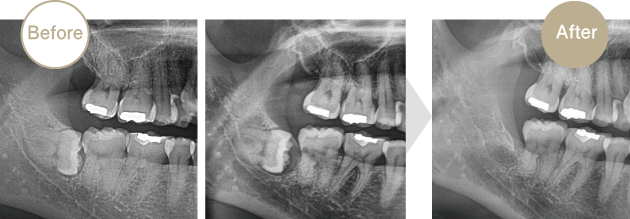

横を向いて倒れていることが多い親知らずは、その歯そのものには問題がなくても手前の歯に虫歯を作ってしまうケースがあります。上から見て虫歯がなくても、気づかない間に親知らずと接している部分に虫歯を作ってしまうのです。その疑いがあれば抜歯の適応となります。レントゲンで見つかる事が多いので、定期検診をおすすめします。